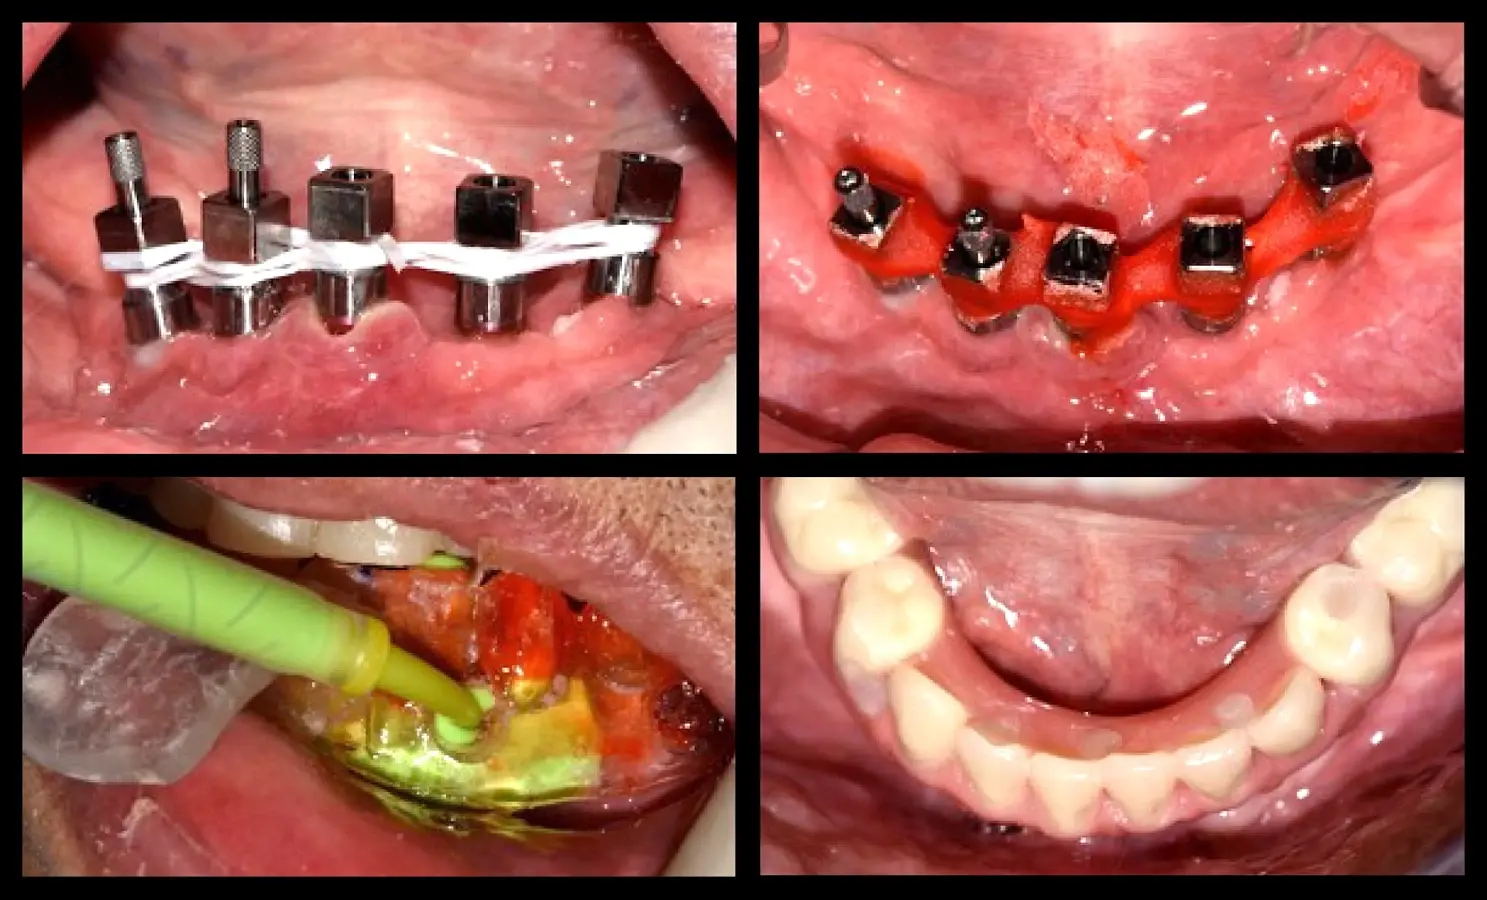

Paciente de ochenta y dos años de edad, de sexo masculino, acudió a la consulta odontológica refiriendo la necesidad de una prótesis inferior y malestar con la prótesis fija superior maxilar. El paciente refirió que le diagnosticaron diabetes mellitus tipo 2 hace 15 años. Refirió también haber tenido carcinoma de próstata y haber recibido radioterapia, hormonoterapia y orquiectomía. La última dosis de radioterapia la había recibido hace 72 meses y fue de 78 Gy en total. El paciente tenía un ASA2 según la clasificación del estado físico de la Sociedad Americana de Anestesiología (ASA)8,9. Asímismo, autorizó la recolección de la información y el uso de fotografías para su publicación con la firma de un consentimiento informado. En la evaluación intraoral, se observó coronas metal cerámicas tipo veneer en las piezas superiores con mala adaptación, acúmulo de placa bacteriana y edentulismo mandibular. Se inició el tratamiento con la motivación e instrucción de higiene oral, se procedió con la eliminación de las bolsas periodontales mediante raspado y alisado radicular. Estabilizada la salud periodontal, se realizó el alargamiento de las coronas clínicas. La gingivectomía se realizó con el electrobisturí (Servotome, Acteon), mientras que para el remodelado óseo se utilizaron los insertos P2LD del piezoeléctrico (Piezomed, W&H) (Figura 2).

Recontorneo gingival

Figura 2. Recontorneo gingival y alargamiento de corona clínica mínimamente invasiva mediante cirugía piezoeléctrica, donde se remodela el hueso sin elevar grandes colgajos (a). Se utilizaron los insertos de piezoeléctrico P2LD de W&H (b).

El procedimiento quirúrgico se inició con la asepsia y antisepsia del campo operatorio y del paciente. A continuación, se colocó anestesia infiltrativa a nivel de la proyección de salida de los agujeros mentonianos, se procedió con la incisión y decolado. Se realizó la delimitación y regularización del reborde óseo mediante el inserto aserrado B7 y el subsiguiente remodelado del reborde crestal mediante el inserto plano diamantado S1 del piezoeléctrico Piezomed (W&H) (Figuras 4 y 5).

Remodelado óseo

Figura 4. Remodelado óseo mínimamente traumático realizado con tecnología piezoeléctrica.

Se realizó la preparación del lecho periimplantar según el protocolo del fabricante (Unitite, S.I.N.). La secuencia de preparación de los implantes implicó la primera preparación del implante en posición C, en concordancia con la línea media del paciente, y que nos sirvió de guía para la preparación de los demás lechos quirúrgicos. Los siguientes lechos quirúrgicos preparados fueron los distales (Posición A y E); dicha preparación fue orientada hacia distal para mejorar la distancia antero-posterior y reducir así el efecto de palanca distal; finalizando con los de posición B y D. Se colocó la guía quirúrgica para revisar la emergencia en relación a la superficie oclusal de los dientes. La secuencia de fresado del fabricante (UNITITE, S.I.N.) es fresado intermedio, en donde el diámetro de la fresa final es 0.20 mm menor al diámetro del implante. El fresado intermedio reduce la cantidad de microfisuras a nivel de las roscas del implante, y favorece la neoformación ósea a nivel de las cámaras de cicatrización. Procedimos con la colocación de los implantes de 3.5 mm de diámetro y 10 mm de longitud (UNITITE, S.I.N.) (Figura 6).

Colocación de implantes dentales

Figura 6. Colocación de implantes dentales con superficie activada.

La segunda fase quirúrgica y colocación de pilares intermedios fue realizada en la semana 18, siguiendo la recomendación del fabricante con un torque de 20 Ncm. Se realizó la impresión del maxilar superior y la transferencia de los implantes del maxilar inferior. Una vez corroborado el asentamiento de ambas estructuras en boca se envió al laboratorio para el enfilado de la estructura inferior. Finalizada la prótesis fue instalada en el paciente (Figura 10).

Rehabilitación fina

Figura 10. Rehabilitación final: toma de impresión mediante la técnica de la guía multifuncional.